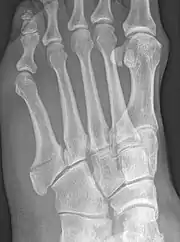

Robert Jones described the fracture of the fifth metatarsal which bears his name in the Annals of Surgery in 1902. In his paper, Jones described the fracture in a series of six patients, the first of which was himself.[8] He had injured his foot while dancing several months earlier, and had thought the injury to be to a tendon in the foot. He examined himself the day after the injury, and found that the tendon was intact, but he could not find definite evidence of bony injury. He asked a colleague, David Morgan, to X-ray his foot, and a fracture above the base of the fifth metatarsal was found. The finding of similar fractures in several patients after his own prompted him to write about it. He also noted that the fracture was not caused by direct trauma to the bone, as had always been assumed before, but by a cross-strain being applied to the bone.[9]